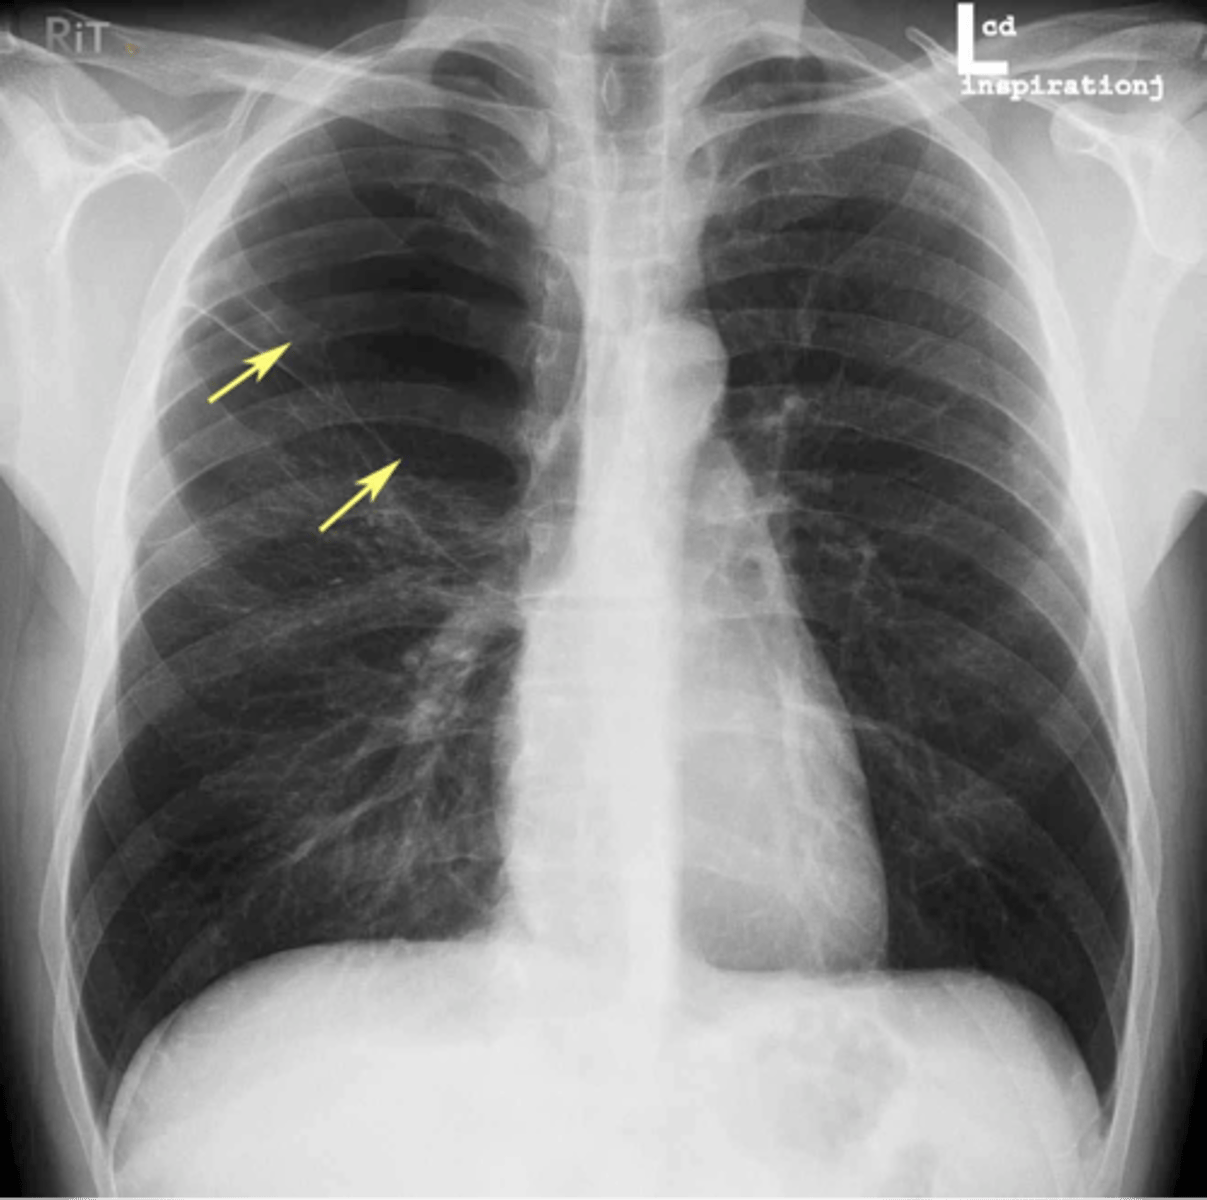

Walls of the bronchi thickened by inflammation or infection, may be diffuse or focal

Bronchiectasis

CXR in affected individuals is often normal or shows non-specific findings

Bronchiectasis

Bronchiectasis

Tram track lines

Bronchiectasis

Asthma (hyperinflation with tram lines)

asthma